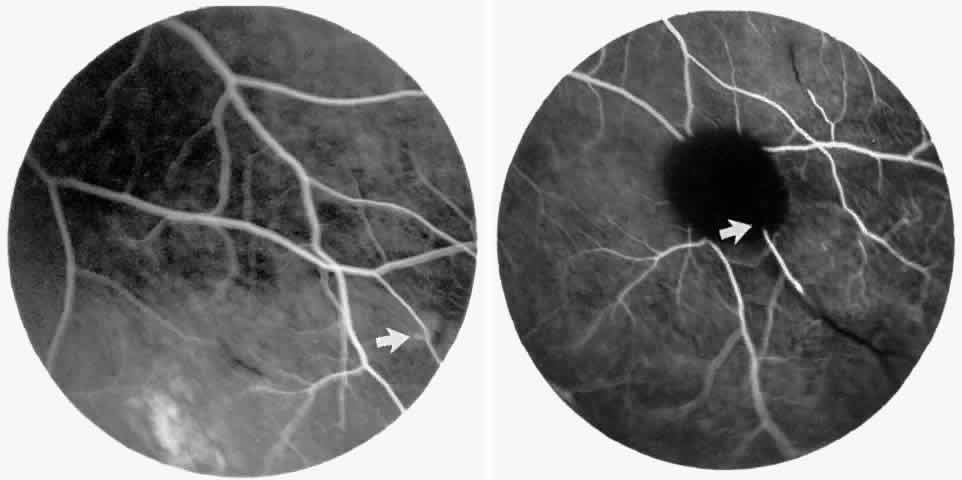

The occluded arterioles may be invisible or may have a “silver-wire” or chalk-white appearance, as first described by Goodman and colleagues39 (Fig. 21). Fluorescein angiography may demonstrate an abrupt complete occlusion at the interface between peripheral nonperfused and posterior perfused retina. Frequently, this occlusion will take place just distal to a branching vessel, giving the appearance of a freshly pruned rose bush. The nonperfused anterior peripheral retina will have a grayish brown appearance and on fluorescein angiography will appear blurred without clearly defined fundus markings.

Fig. 21. A. Photograph of the peripheral retinal vasculature shows sheathed vessels and absence of peripheral vascular perfusion. B. Fluorescein angiogram shows area of nonperfusion representing stage I sickle cell retinopathy. White arrow points to corresponding vascular bifurcation in A and B.

STAGE II: PERIPHERAL ARTERIOLAR-VENULAR ANASTOMOSES. Following occlusion of the terminal arterioles, anastomotic channels form to channel the blood from the occluded arteriole to the nearest venules. These anastomoses form at the interface between the perfused and nonperfused retina. Most likely, they are dilated preexisting capillaries rather than new vessels, since they do not leak on fluorescein angiography. The redirection of blood flow is probably due to hydrostatic forces (Figs. 22 and 23).

Fig. 22. A. Photograph of the peripheral retina, demonstrating capillary occlusions and exudate at the margin of perfused retina. B. Fluorescein angiogram of irregular capillary border, with capillary stumps extending into nonperfused retina and an arteriolar-venular anastomosis demonstrating stage II retinopathy.